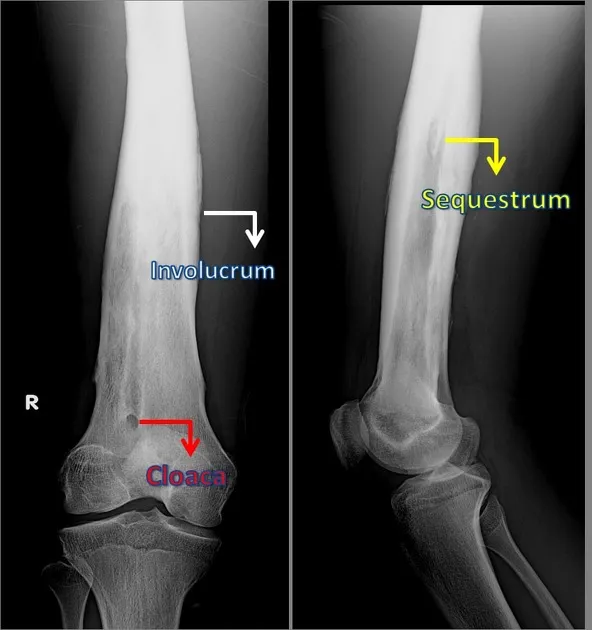

- Chronic: Sequestrum (necrotic bone), involucrum (new bone shell), cloaca (opening).

- 📌 SICK bones: Sequestrum, Involucrum, Cloaca, Know it's chronic!

- Chronic osteomyelitis: characterized by sequestrum, involucrum, cloaca.